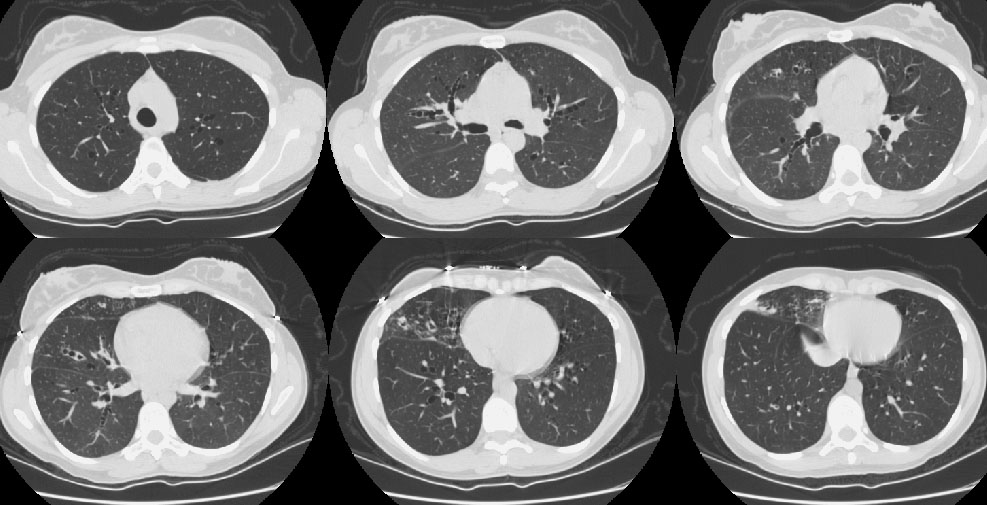

Scott WilliamsAutoimmuneAutoimmune > Amyloid > ImagesApril 2, 2002CardiacCardiac > Valve > MVP > ImagesApril 2, 2002EndocrineRadionuclides in Thyroid ImagingApril 2, 2002Central Nervous SystemCNS > Conventional imagingApril 2, 2002CardiacCardiac > Adultdz > CACalcApril 2, 2002Vascular AbnormalitiesVascular > PEApril 2, 2002Infections-InflammatoryInfect > Fungus > CocciApril 2, 2002Miscellaneous PulmonaryMisc > Bronchiectasis > Images > Case2April 2, 2002Mediastinal MassesMediastinum > Germcell > Images > Benign Germ Cell Tumor Case 1April 2, 2002TumorTumor (T) Examples Primary Tumor (T)April 2, 2002Previous PagePage 101 of 265Next PageTop StoriesDigital X-RayChest x-rays reveal atherosclerosis in patients undergoing amputationsLower limb amputation is an increasingly common major complication of advanced peripheral arterial disease and diabetes mellitus.MRI3D MRI technique helps plan treatment for pediatric heart conditionsWomens ImagingCould AI scoring help with managing DCIS?CTClinicians, beware: CT diagnostic accuracy varies by adnexal lesion typePractice ManagementRadiology coding update for 2026